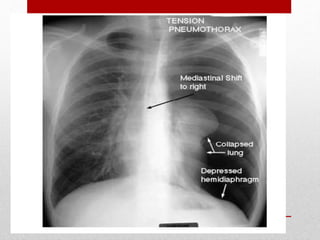

Tension pneumothorax

• presumed in any patient manifesting

respiratory distress and hypotension

in combination with any of the

following physical signs:

• tracheal deviation away from the

affected side

• lack of or decreased breath sounds

on the affected side,

• subcutaneous emphysema on the

• Distnded neck veins

• Tube thoracostomy in the

midaxillary line should be

performed immediately in the

ED before a chest radiograph

is obtained.

• Recent studies suggest that

preferred location for needle

decompression may be the

fifth intercostal space in the

anterior axillary line due to

body habitus.